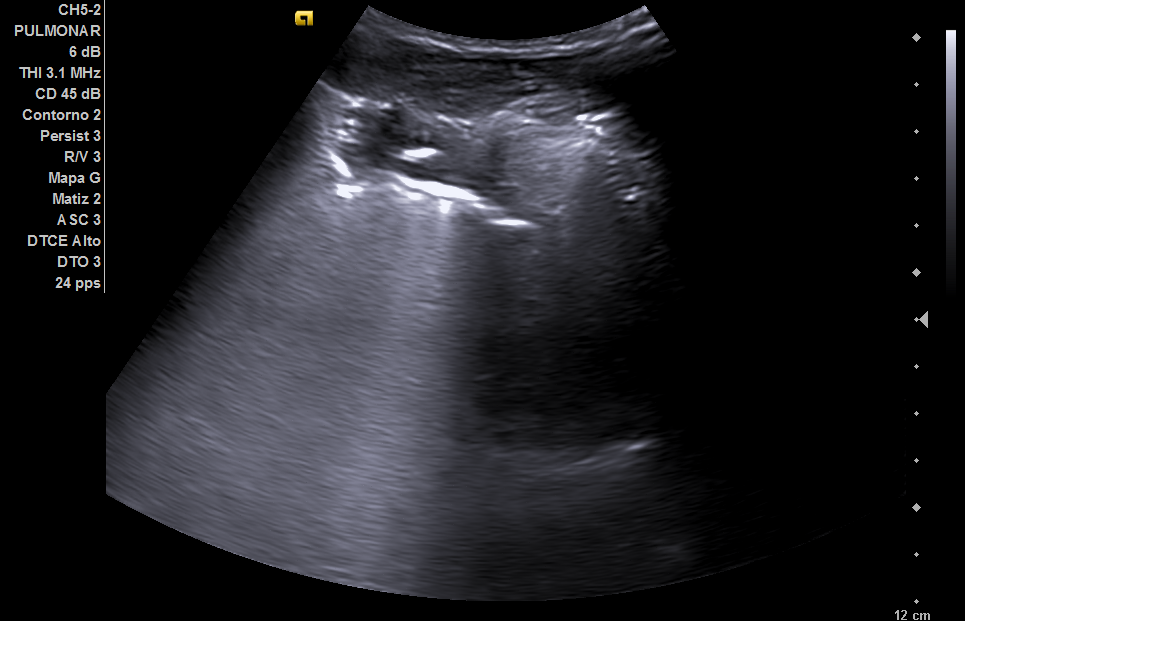

Escolar hombre de 5 años con vacunación reglada sin antecedentes médicos. Consulta por fiebre de tres días de evolución, de hasta 39.5º, que cede con antitérmicos. Asocia tos productiva y ligero decaimiento. En la exploración física, presenta triángulo de evaluación pediátrica estable, auscultación pulmonar con hipoventilación y crepitantes en la base pulmonar derecha, sin distrés respiratorio ni taquipnea ni desaturación. El resto de la exploración física por aparatos fue anodina. Se realiza ecografía pulmonar con sonda convex y lineal, donde se observa hepatización de la base pulmonar derecha, compatible con consolidación de 3 x 2,5 cm y líneas B en la zona circundante, sin derrame pleural.

Se realiza seguimiento en el propio Centro de Salud dos días después de iniciar tratamiento antibiótico, con mejoría clínica y auscultatoria del paciente. Ecográficamente, se aprecia lengüeta de líquido en seno costofrénico derecho de menos de 1 cm. En seguimiento tras una semana de antibiótico, resolución completa del cuadro clínico sin complicaciones, con auscultación normal.